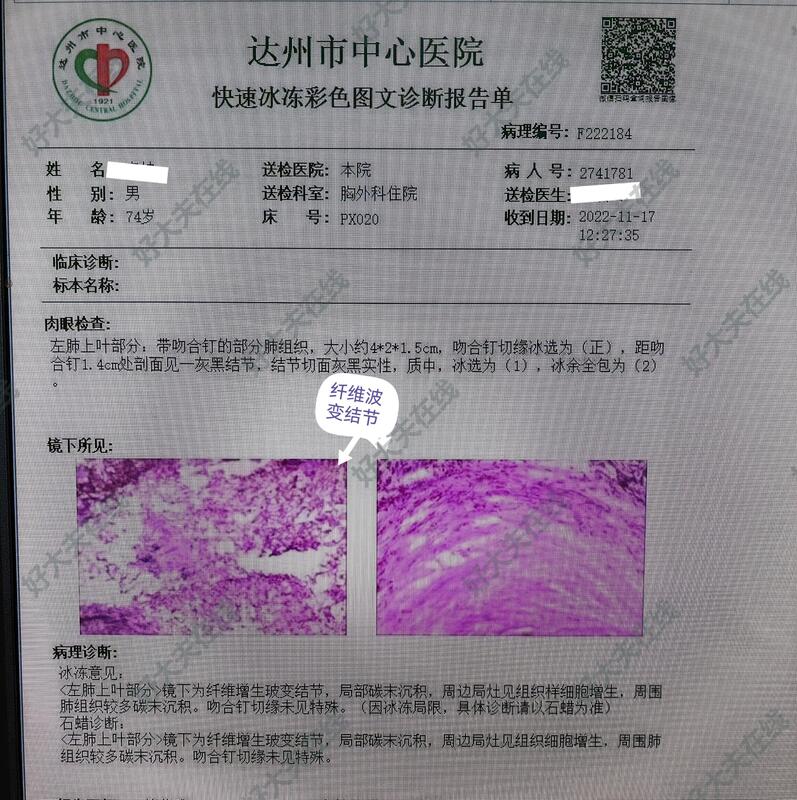

图6-10,男性,74岁,体检发现左肺上叶尖后段结节,亚实性磨玻璃样,毛刺、分叶、胸膜牵拉等,也短期随访,结节不改变,自身和子女的心里压力大(一月内反复不同医院做CT等)。胸腔镜微创手术切除,术中:整个胸膜腔完全闭锁粘连,彻底游离粘连,予以左上肺结节切除,病理报告为良性病变。

例2,70岁,男性,系良性病变,肺质量差,建议戒烟,注意预防肺部感染。定期医院随访。

所传照片系第二例病人拔管时的胸片。